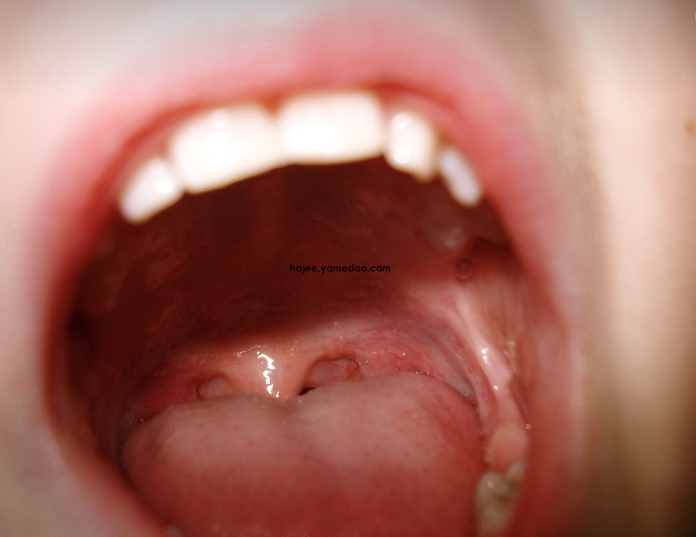

혓바늘은 혀에 생기는 작은 염증이나 궤양을 뜻하는데, 통증이 심하고 불편함을 유발할 수 있습니다. 혀의 특정 부위가 붉어지거나 흰색으로 변하면서 따끔거리거나 쓰라린 느낌이 드는 혓바늘이 돋는 이유 10가지 알아보도록 하겠습니다.